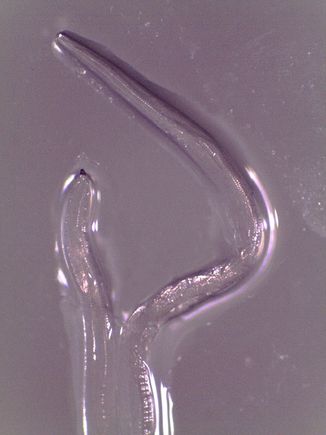

Thelazia life cycle

Thelazia life cycle. (CDC.gov/dpdx)

Worms in the family Thelazia are a common parasite in North American cattle, but are rarely spread to humans. Before this case, there were just 10 known incidences of humans being infected with a Thelazia worm in North America, but none of those cases involved the species gulosa. This was the first case of a person being infected with a Thelazia worm in the U.S. in more than two decades.

The best Bonura and her colleagues can guess is the patient, Abby Beckley, may have been infected while being near cows or horses in the rural fields near her family’s home. The cattle eyeworm is spread from cow to cow by flies that suck on cow tears and pick up worm larvae in the process. One fly carrying cattle eyeworm larvae may have briefly landed on the patient’s eye.